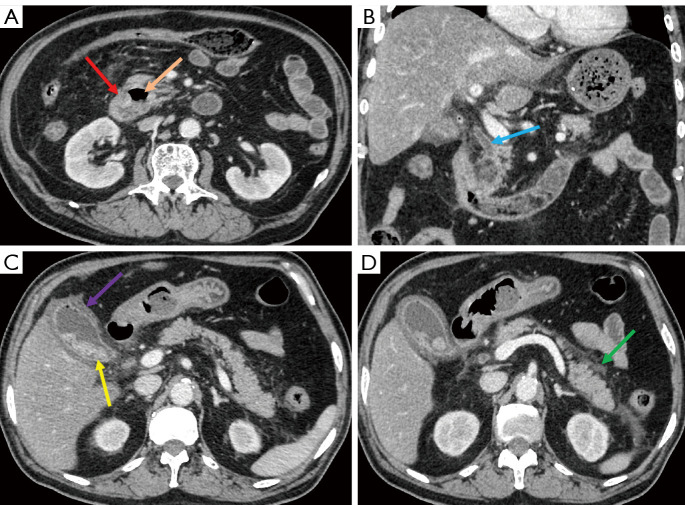

Results: Patients with HRPAD were significantly older than those with N-HRPAD, with an average age of 72±10 and 68±11 years, respectively (P<0.001). Additionally, they exhibited a higher proportion of larger diverticula (>1.95 cm: 65.38% vs. 22.57%), larger common bile duct (CBD) size (>0.69 cm: 72.31% vs. 20.83%), and greater pancreatic duct (PD) dilation (>0.20 cm: 86.92% vs. 60.42%) (all P values <0.001). Furthermore, there was a greater prevalence of diverticular neck swelling in the HRPAD group than in the control group (23.08% vs. 4.86%; P<0.001). Binary logistic regression analysis indicated that a diverticulum size >1.95 cm, CBD size >0.69 cm, PD size >0.20 cm, and the presence of diverticular neck swelling were predictors significantly associated with HRPAD, yielding an area under the curve (AUC) of 0.848; meanwhile, the AUC of the external validation cohort was 0.829.

Conclusions: Patients with HRPAD and those with N-HRPAD exhibited different clinical and imaging characteristics. A thorough understanding of these differences may facilitate early identification of HRPAD and timely treatment interventions, which would reduce complications related to biliary-pancreatic diseases.